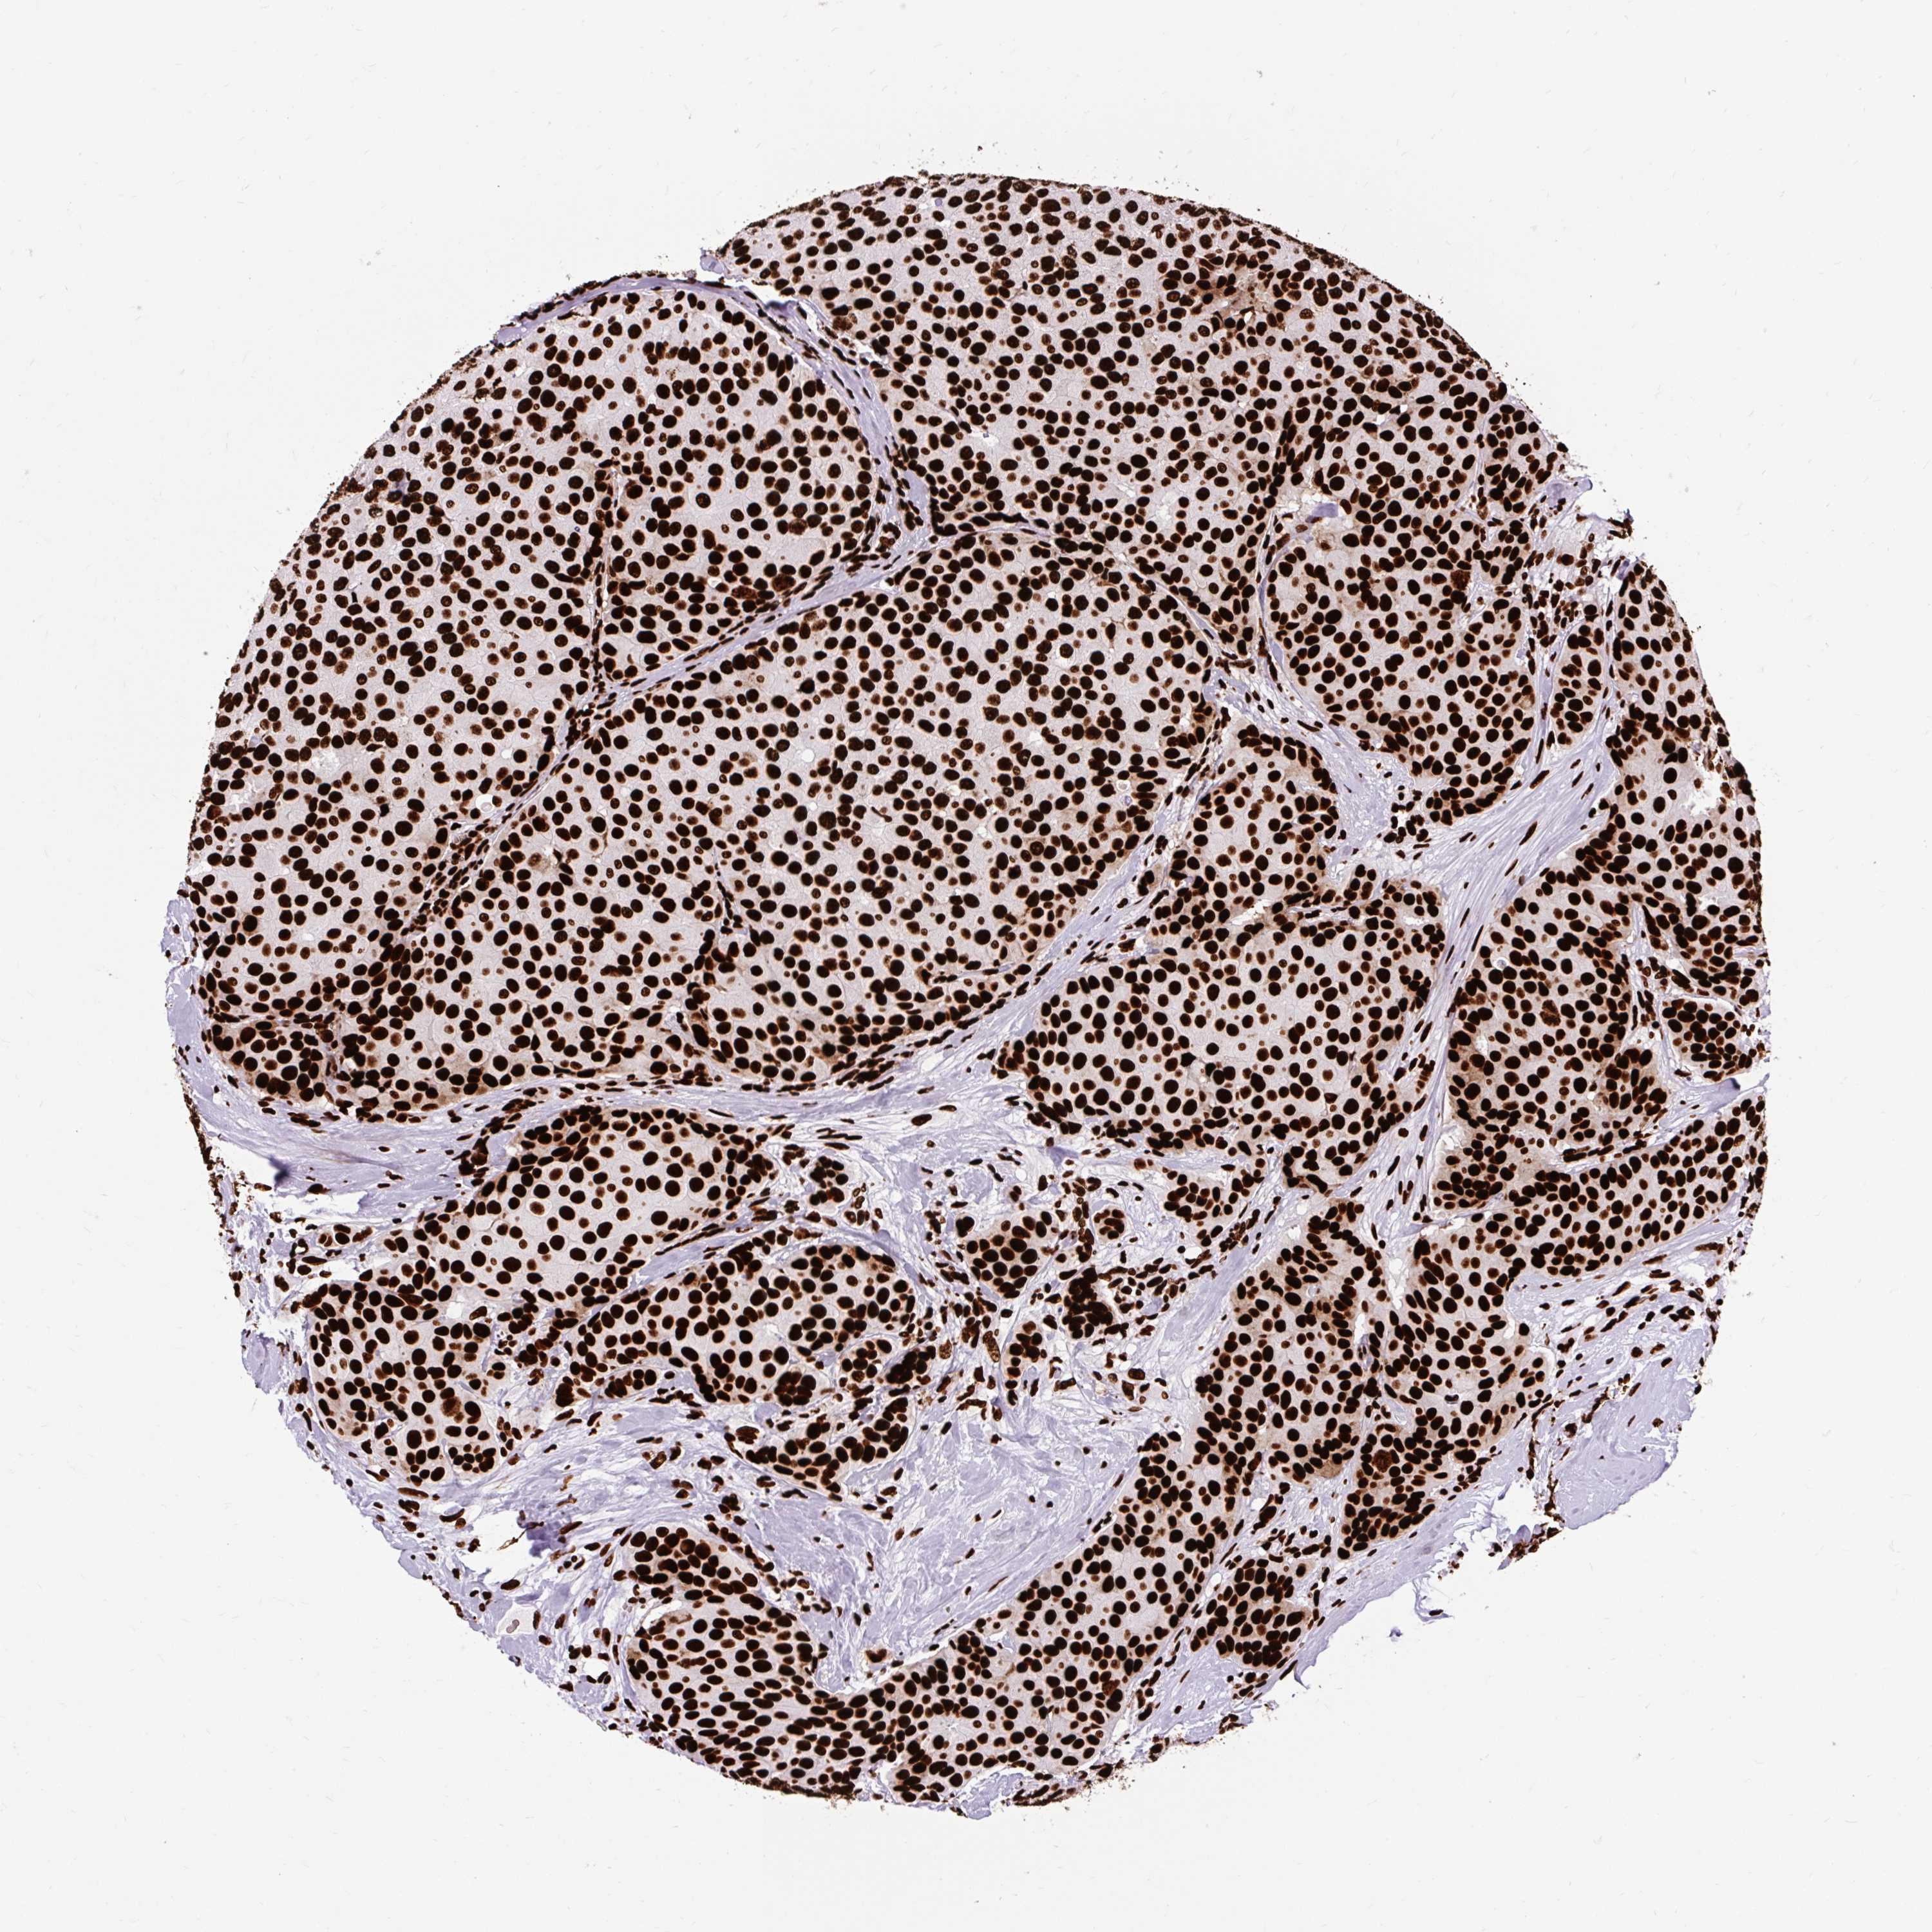

BRCA TCGA BRCA VALIDATION PROTEIN EXPRESSION